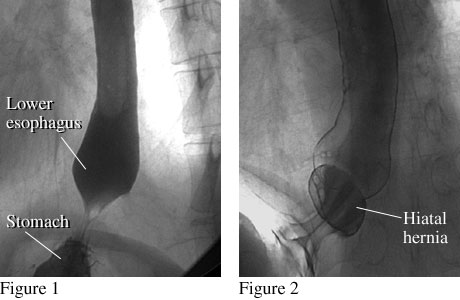

Figure 1 shows the lower end of a normal esophagus with a smooth connection between the lower esophagus and stomach. Figure 2 shows the lower end of the esophagus with a small hiatal hernia, which occurs when a small portion of the stomach pushes up into the chest.